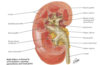

venous drainage of kidney

R & L renal V

- anterior to A

- L receives L suprarenal and L gonadal

drain to IVC

L passes anterior to aorta, posterior to desc SMA

Peri-nephric abscess

spread to pelvis due to fascial attachment

- DOES NOT SPREAD TO ADJ KIDNEY

causes:

- UTI

- staph aureus

- DM

- lsions of urinary tract: stones, cyst